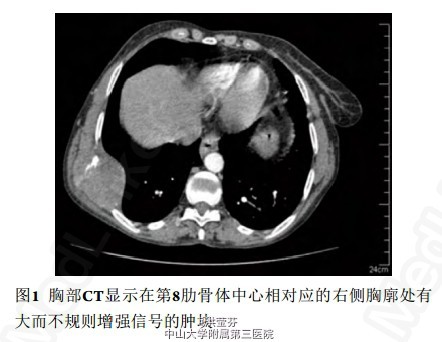

体格检查:右前胸壁(第7和第8肋骨高度)存在结节状、非活动的、有触痛的皮下团块。胸片显示右下胸部的大肿块,同时伴有第6和第7肋骨的部分骨破坏。CT显示在第8肋骨体中心相对应的右侧胸廓处有大而不规则增强信号的肿块,大小为6.9 cm ×4.4 cm ×5.7 cm。它侵犯了前锯肌和胸膜外脂肪,很少波及到内侧的肺组织(图1) 。脑及腹部-骨盆CT扫描未发现异常改变。进行细针穿刺活检,组织学结果显示恶性肉瘤(图3~4)。